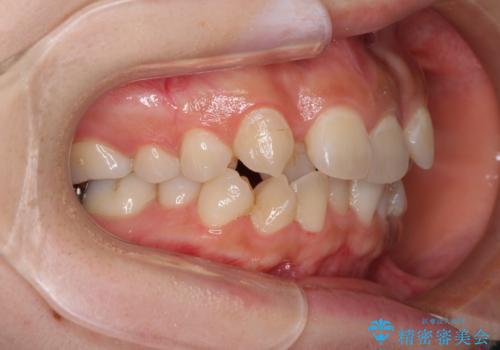

- 前歯の著しいデコボコを気にして来院された患者様です。

上顎の左右側切歯(前から2番目)が裏側に隠れいてる状態で、咬み合わせや清掃性に大きな問題が認められました。

左下に八重歯があったそうですが、当時は矯正治療を行うことを考えていなかったため、抜歯してしまったとのことでした。

叢生が著しいため、左下以外の第一小臼歯3本を抜去し、目立たないワイヤー装置にて矯正治療を行うこととしました。